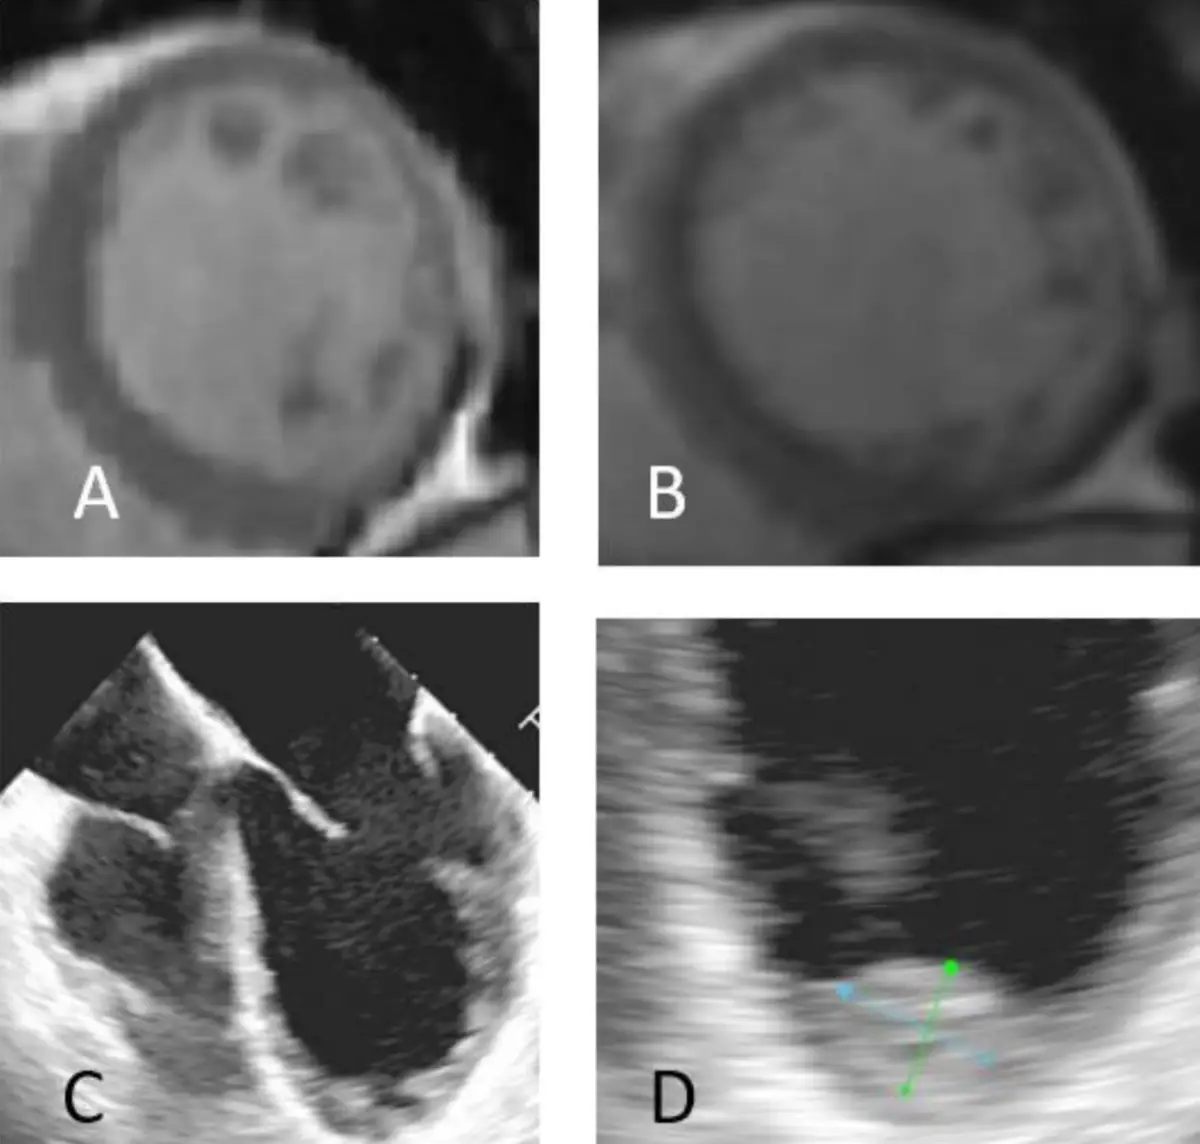

一位55歲女性病患因端坐呼吸與動喘一週而來住院。身體診察發現血壓90/56毫米汞柱,心跳每分 鐘102下,頸靜脈怒張,心音低遠併第三心音,肺部有囉音,雙下肢小腿與腳部水腫。心電圖如圖一。心臟 超音波呈現左心室擴大,瀰漫性左心室收縮功能異常,左心室射出分率(left ventricle ejection fraction)為25%。心臟磁振造影檢查如圖二A與B。經食道心臟超音波如圖二C與D。請問下列敘述何者錯誤? (1)該病患的心電圖呈現 low voltage in frontal leads (2)該病患心電圖呈現心房顫動 (3)該病患之心臟磁 振造影影像檢查呈現左心室心肌緻密化不全(left ventricular non-compaction) (4)該病患之心臟磁振造影影 像檢查呈現急性心肌發炎 (5)該病患應使用口服抗凝血劑 (6)這種疾病有時是因肌節(sarcomere)基因異常 引起 圖片描述 圖片描述

2. CMR (A, B):短軸切面可見左心室內層密集的放射狀粗大小梁與深凹陷,外層致密心肌薄;非緻密/緻密層厚度比肉眼明顯大於 2.3,無明顯線性延遲增強 (late gadolinium enhancement) 支持急性心肌炎。

3. 經食道心臟超音波 (C, D):四腔及短軸觀顯示心尖與側壁大片海綿狀小梁,小梁間灌注與左心室腔相通,測量箭頭標示非緻密/緻密層比值明顯升高;室腔擴大、收縮扭動減弱,與低 EF 相符。